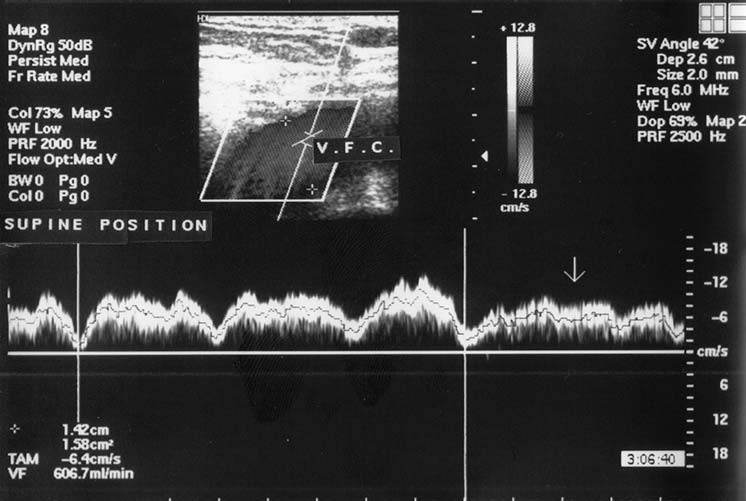

При исследовании в цветовом допплеровском режиме просвет вены полностью прокрашивается. В положении лёжа выявляется ламинарный антеградный поток. В допплеровском импульсно-волновом режиме также регистрируется антеградный поток с фазами, совпадающими с дыханием (снижается на вдохе и увеличивается на выдохе). Это отражает феномен «vis a fronte» (совокупность факторов, влияющих на «присасывание» венозной крови в положении лёжа). Волна допплеровского венозного спектра состоит из более коротких волн, синхронизированных с частотой сердечных сокращений, что отражает один из элементов венозного возврата — присасывающее действие сердца (рис. 1).

Рис. 1. Кровоток в бедренной вене в спектральном допплеровском режиме в положении лёж

Доказательством того, что данные волны отражают именно присасывающую функцию правого предсердия, а не передаточную пульсацию расположенной рядом артерии, служит тот факт, что этот феномен регистрируется также и у пациентов с окклюзией расположенной рядом артерии.

При проведении пробы с задержкой дыхания на выдохе допплеровский спектр венозного кровотока становится менее амплитудным, без чётко выраженных волн, с колебаниями, связанными с частотой сердечных сокращений. Это отражает ещё один компонент венозного возврата — фактор «vis a tergo» (остаточная сила сердечного выброса) (рис. 2).

Рис. 2. Кровоток в бедренной вене в спектральном допплеровском режиме при задержке дыхания на выдохе (стрелка)